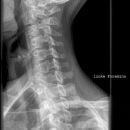

Halswirbelsäule lateral

Technik

• FDA: 1,15 m

• Ausgangsformat: 24/30

• mit Raster

Lagerung

aufrecht sitzend am Stativ

Arme seitlich hängend, aktiv nach unten ziehen lassen

Kopf gerade und Kinn leicht angehoben

Zentralstrahl

ZS senkrecht auf Objekt- und Detektormitte

Quer: 2 QF unter Kieferwinkel

Längs: ca. Processus mastoideus

Tiefenblende anpassen

Einblendung

oberes Licht Tragus, lateral Prominens im Licht

Qualitätskriterien

Alle 7 HWK lateral dargestellt, orthogonale Darstellung der Grund- und Deckplatten, Processus spinosus des 7. HWK vollständig dargestellt, Mandibula überdeckt HWS nicht.